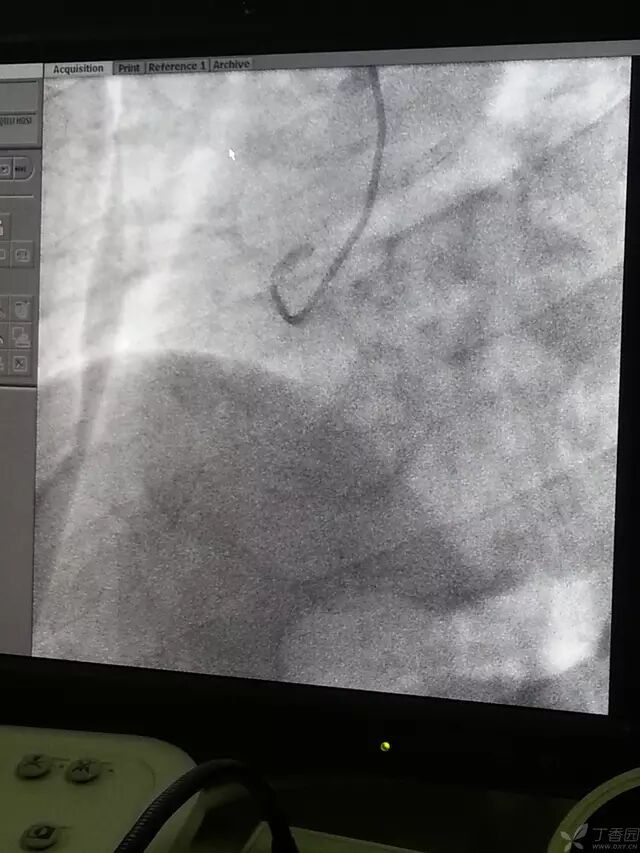

将造影导管头端塞入鞘管头,助手送入导丝,当外露导丝 10-15 cm时,踩线,小步快走送入造影导管,当进入锁骨下动脉时,如下图。

造影导丝是什么原来心脏造影这样做:冠脉造影全程图解_https://www.jmylbn.com_新闻资讯_第11张

可嘱病人深吸气并憋住,一般导丝可顺利进入升主动脉,下降至窦底,使导丝盘成 L 型时,如下图。